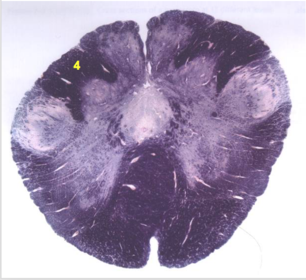

| Longitudinal pontine fibers (corticospinal tract) | |

| Transverse pontine fibers (dark fibers) | |

| Pontine nuclei (pale) | |

| Medial lemniscus | |

| ALS | |

| Trapezoid body | |

| Ventral trigeminothalamic tract | |

| Superior olive | |

| Central tegmental tract | |

| Facial nerve root fibers - descending | |

| Facial motor nucleus | |

| Interposed nuclei | |

| Medial longitudinal fasciculus | |

| Facial nerve root - internal genu | |

| Abducens nucleus | |

| Lateral vestibular nucleus | |

| Superior vestibular nucleus | |

| Inferior cerebellar peduncle | |

| Superior cerebellar peduncle | |

| Dentate nucleus | |

| Fastigial nucleus | |

| Anterior spinocerebellar tract | |

| Spinal nucleus of V | |

| Spinal tract of V | |

| Middle cerebellar peduncle | |